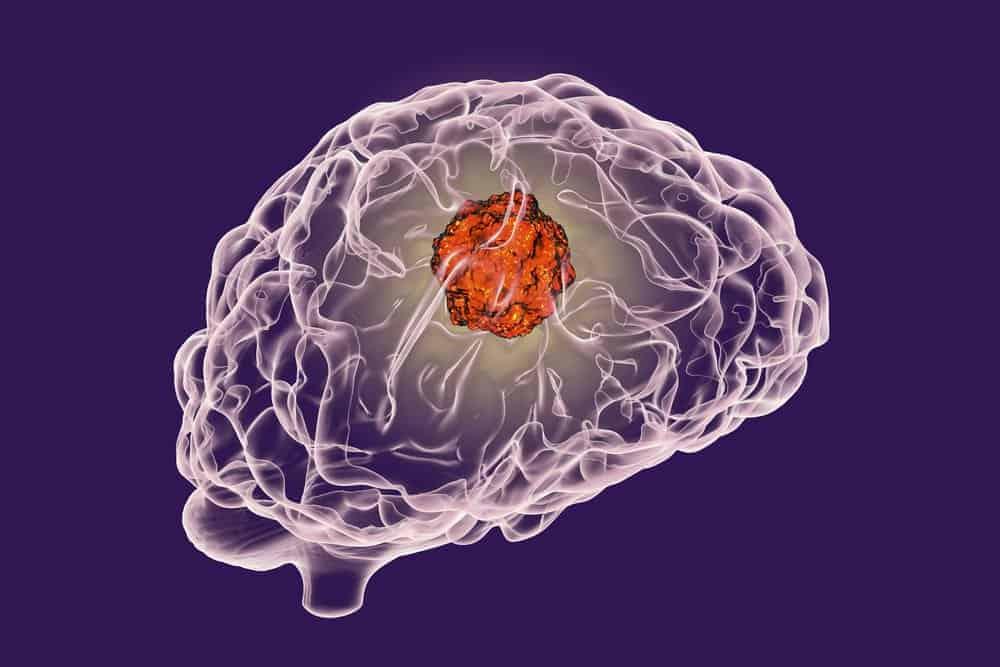

U sao bào, hay còn gọi là u não tế bào hình sao là những khối u phát sinh từ tế bào hình sao. Tế bào hình sao có chức năng tạo nên tế bào mô đệm hoặc mô nâng đỡ của não. Não là cơ quan chính của hệ thần kinh trung ương, não được tạo thành từ các tế bào thần kinh (neuron) và mô hỗ trợ (tế bào mô đệm).

U sao bào có thể xuất hiện ở các bộ phận khác nhau của não và hệ thần kinh, bao gồm tiểu não, đại não, các vùng trung tâm của não, thân não và tủy sống.